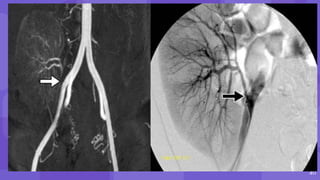

• #16 Postbiopsy pseudoaneurysm and arteriovenous fistula (AVF) Color Doppler image shows a round area of bidirectional flow (arrow) in the upper transplant kidney, consistent with a pseudoaneurysm. Spectral analysis at a site of focal aliasing near the pseudoaneurysm shows high-velocity systolic flow and low-resistance diastolic flow, characteristic features of an AVF Three-dimensional volume-rendered image shows the renal artery (white arrow) with an early draining vein (black arrow) as well as the pseudoaneurysm (arrowhead).

• #17 Image from subtraction angiography shows the pseudoaneurysm (arrowhead) and the early draining vein from the AVF (arrow) Same AVF treated with coil embolization. postprocedure AVFs have been reported in up to 10% of renal allograft biopsies, most of which are asymptomatic with no clinically significant hemodynamic consequences. These cases can be treated conservatively and can be followed up with US as needed, with 70% regressing or resolving spontaneously. Large or symptomatic AVFs resulting in abnormal large or persistent gross hematuria or significant hypertension occur in only 1%–2% of cases and can be treated with catheter embolization